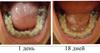

18 дней назад мне устанавливали брекеты на НЧ,недавно хотела сюда писать жаловаться,что ничего не происходит,но зубки как-будто меня услышали и пошли на место!Они у меня такие молодцы,а вот верхние зубки меня не радуют...(

18_dney.jpg